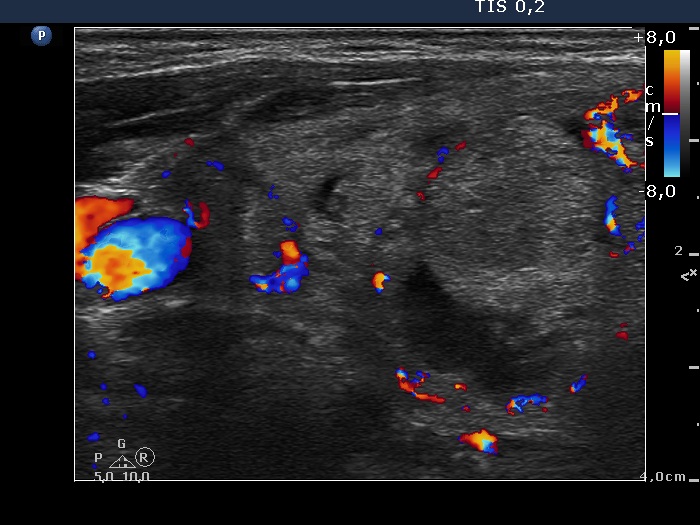

Right lobe, longitudinal scan

Left lobe, longitudinal scan, color Doppler mode. The vascularization is not specific.